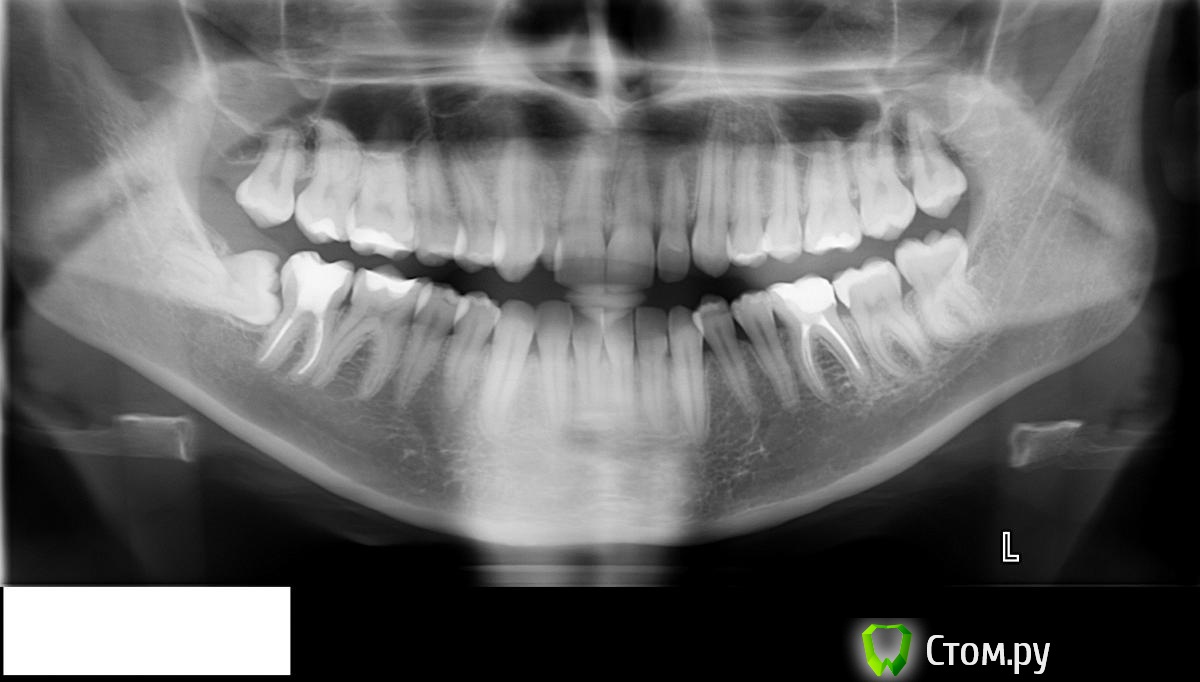

sweettyheart Опубликовано 24 ноября, 2014 Поделиться Опубликовано 24 ноября, 2014 (изменено) Добрый день. Посоветуйте пожалуйста какие зубы нужно удалять и нужно ли для установки брекетов. Сверху справа 7-ка под наклоном, выступает к щеке. 8-ка тоже немного к щеке. Первый зуб справа заходит внутрь, а второй маленький и заходит на первый. Левая часть довольна ровная. У меня предложенное лечение - удалить верхнюю 8-ку справа, затем возможно верхнюю 7-ку справа. А затем нижнюю 8-ку справа.Второе предложенное лечение - удалить 7-ку справа, и тянуть на ее место 8-ку. Затем удалить нижнюю 8-ку справа.Третье лечение - ничего не удалять Изменено 24 ноября, 2014 пользователем sweettyheart Ссылка на комментарий

sweettyheart Опубликовано 7 января, 2015 Автор Поделиться Опубликовано 7 января, 2015 (изменено) Слепки пока нет возможности выложить .Подскажите пожалуйста такой вопрос, вот у меня на НЧ справа зуб мудрости лежит горизонтально под десной . Такие зубы обязательно удаляются ? Изменено 7 января, 2015 пользователем sweettyheart Ссылка на комментарий

red_butler Опубликовано 8 января, 2015 Поделиться Опубликовано 8 января, 2015 Такие зубы обязательно удаляются ? Ваш - удаляйте 1 Ссылка на комментарий